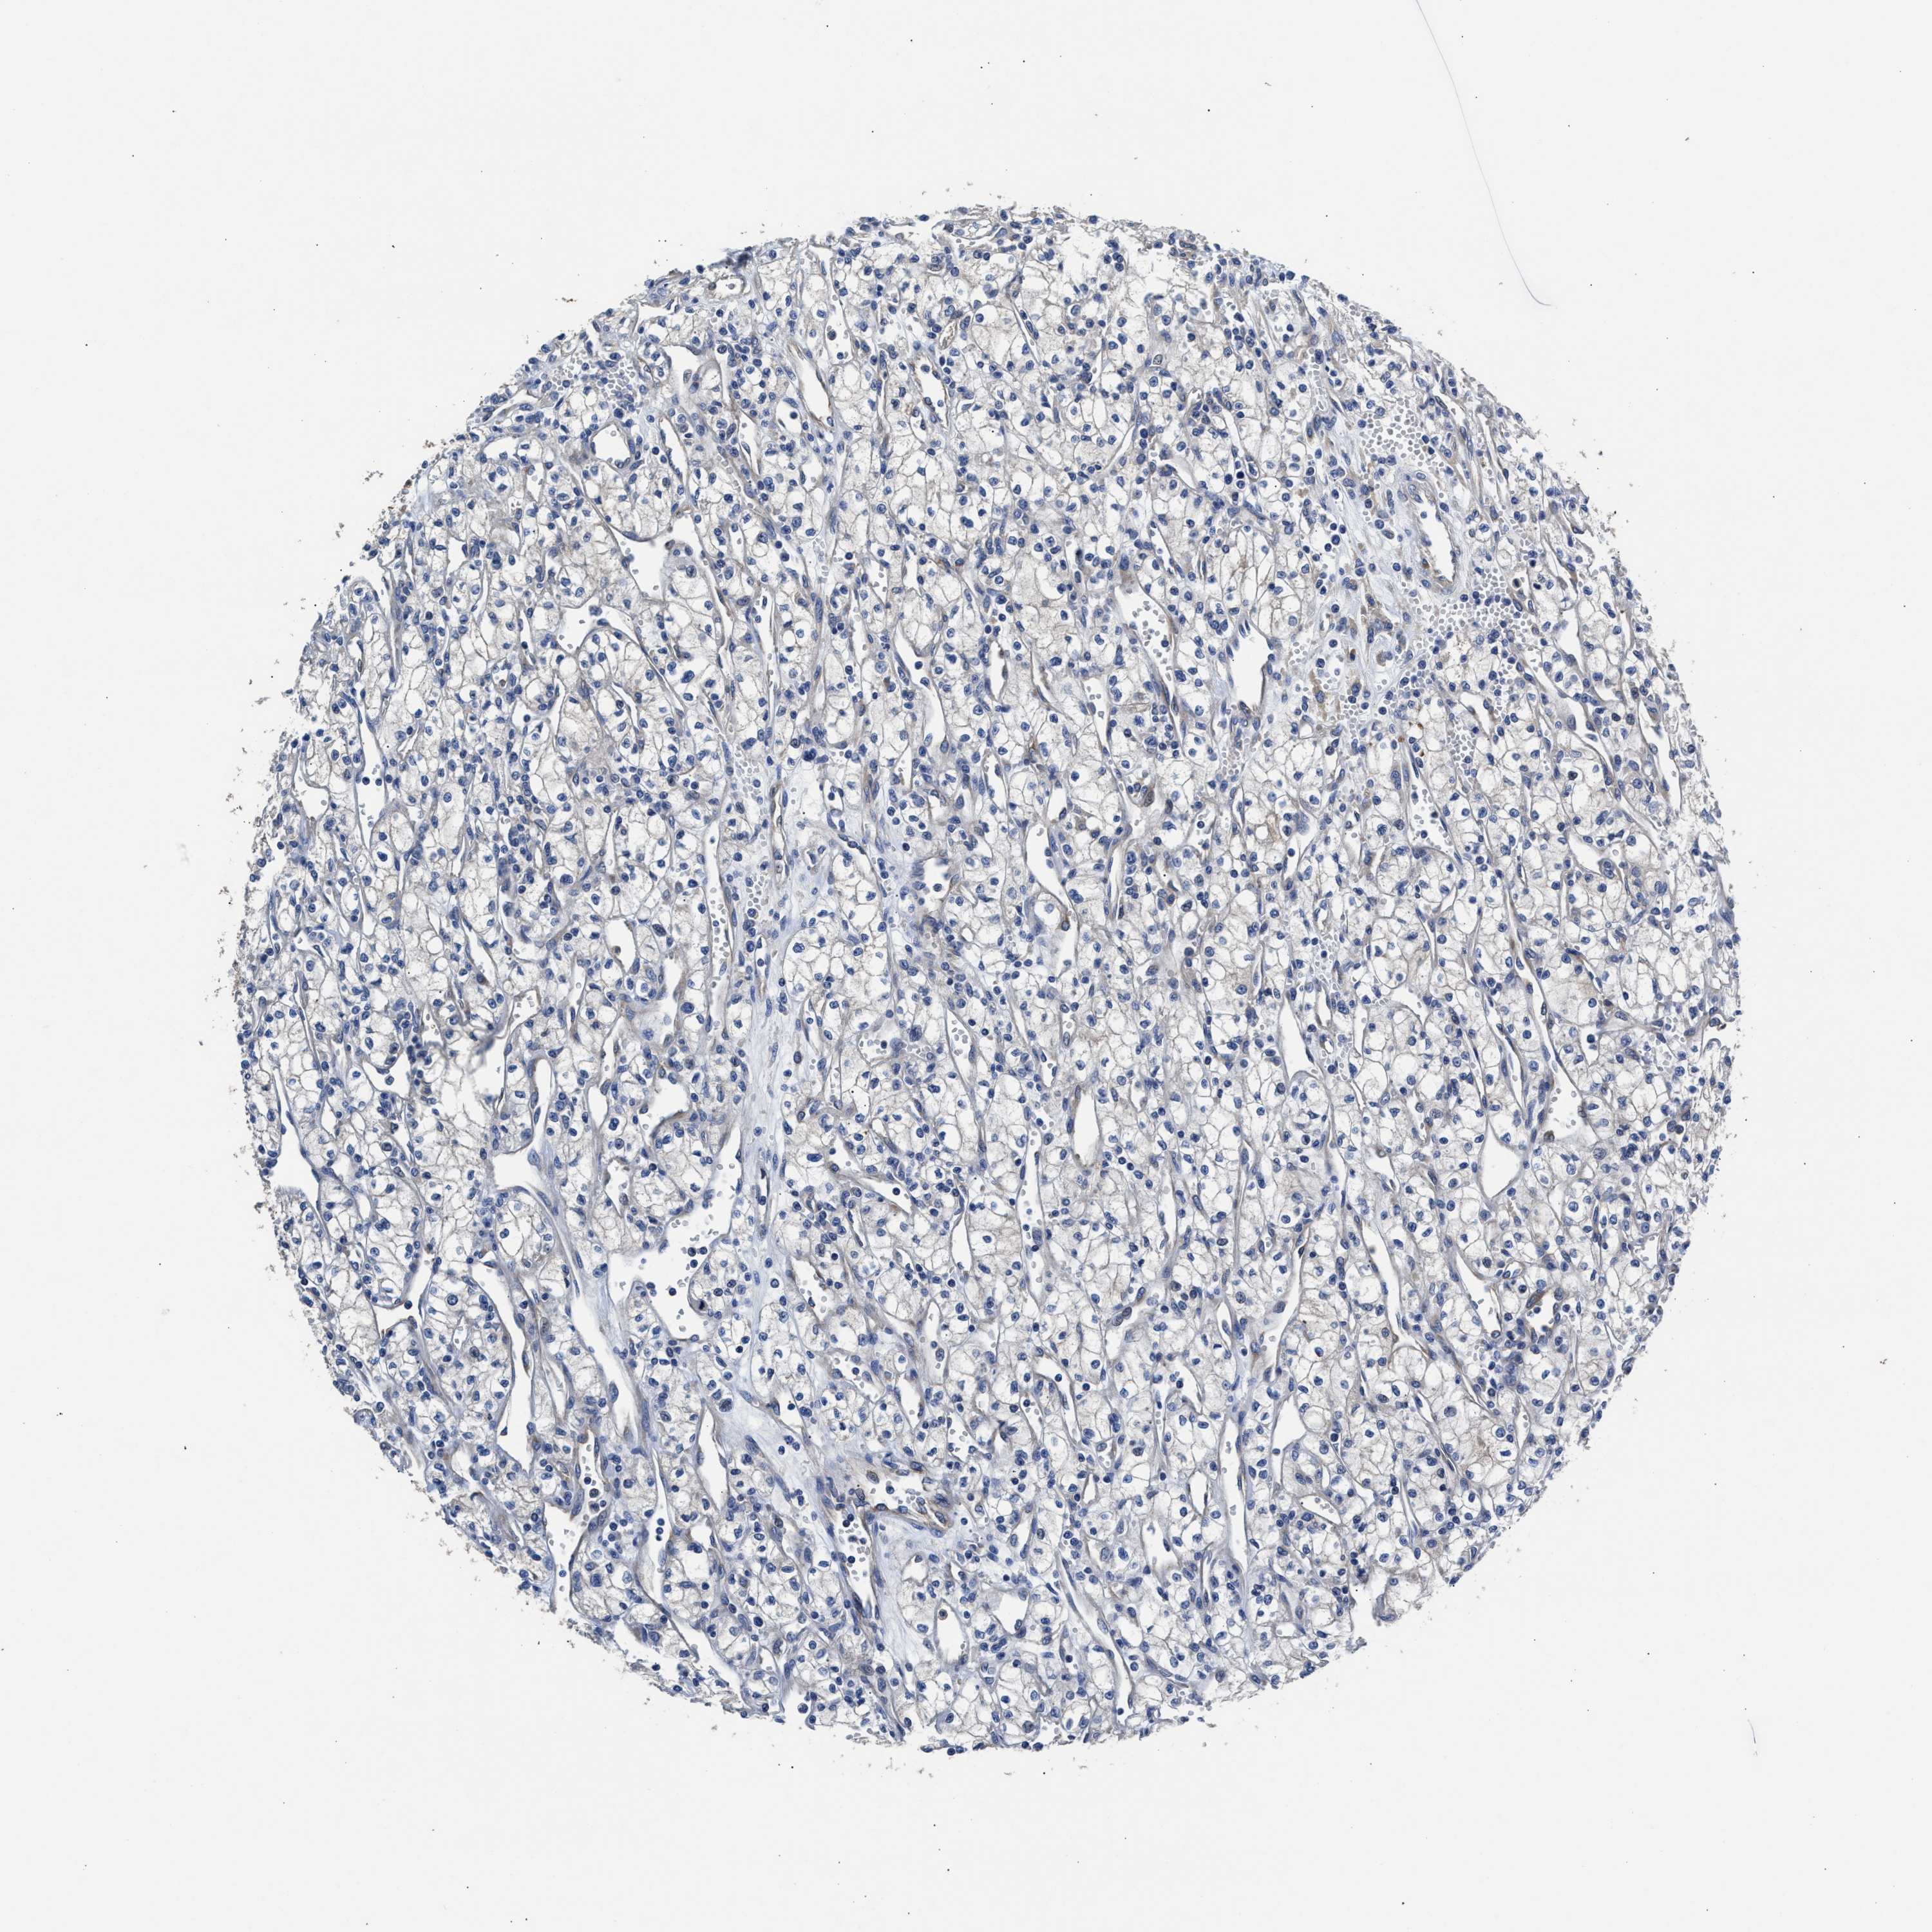

CANCER RENAL CANCER Show tissue menu

KICH TCGA KIRC TCGA KIRC VALIDATION KIRP TCGA PROTEIN RCC CPTAC PROTEIN EXPRESSION

Renal cancer

Kidney renal clear cell carcinoma